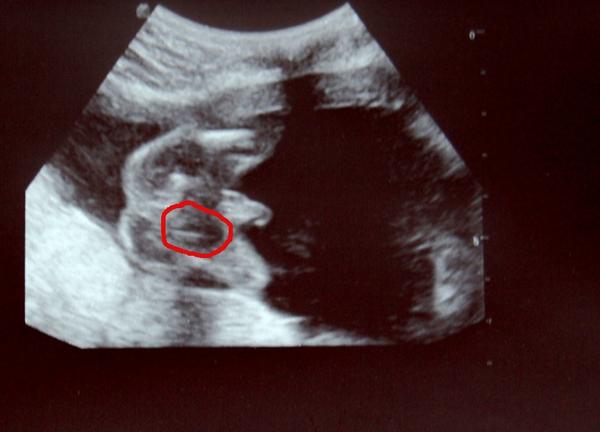

Je to holčička nebo chlapeček? Foto ultrazvuku

Ahoj maminky a budoucí maminky 😉 Prosím, poradila byste mi některá, co vidíte na fotce z ultrazvuku ve 20. týdnu za pohlaví? Určitě jste foteček viděly už mraky, proto vás žádám o radu...Nechci nikoho ovlivnit, proto svůj tip řeknu později 🙂 Děkuju moc!!!

Jestli si někdo myslí, že je to děvče, tak asi vtipkuje. Vždyť je tam vidět jasný pindík a varlátka.

To, co je zakroužkováno, je podle mě varlátko. Když se podíváš na linii zadečku, tak by ji měla jaksi mimo 🙂

doktor mi řekl, že se malé stále mele, že nechce dělat závěry, takže až když jsem naléhala, že to nutně potřebuju vědět 😝 , řekl, že "asi kluk"...jenže jsem pak začala na netu zkoumat fotky z ulztrazvuků a najednou jsem si nebyla jistá, protože ten údajný pindík může být dost dobře také pupečník a najednou jsem viděla zřetelně i to kávové zrno - ale také si myslím, jak píše evitaa, že je trochu mimo osu, jen mě zmátlo, že je zkrátka jasně rozeznatelné. takže jsem z toho prostě jelen a vůbec nevím, co to tedy může být spíše 🙂 z fotky mi přijde, jako když jsou tam pohlaví obě :D

podle mě je to holka, má tam typické ,,kávové zrno´´ což značí holčičku 😉

Jinak když tak koukám na tu tvoji fotku, teoreticky by to mohla být i ta holčička, i když to kávový zrnko není uprostřed. Může to být záběr trošku zboku, tím pádem by to mohlo být maličko posunutý. Ten můj záběr je pěkně zespod, tak nebylo pochyb.

@kajalka Jestli myslíš "čáru" to mnou zakroužkované kávové zrnko, tak to úplně v linii není...ale je tam jiná bílá čárka, to je pravda 🙂 Jen mi to přijde celé nějak šejdrem 🙂 No jsem na to tedy zvědavá, skóre se zvedá 8:5 chlapeček a já jsem čím dál víc v napětí 😀